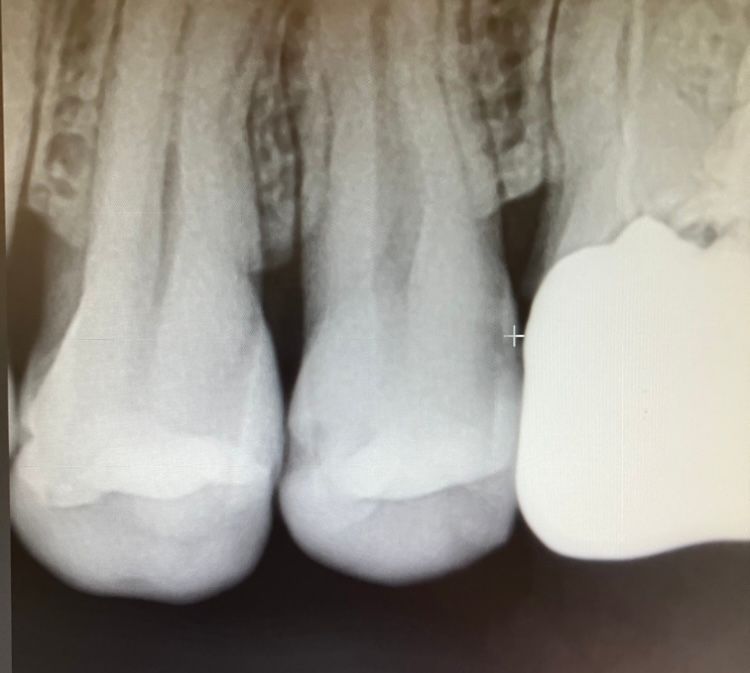

치과에서 송곳니 사이가 썩어서 치료급히 해야한다고 크라운 레인 인레이 고르라고 하더라구요 사이라서 2개를 한꺼번에 해야해서 비용이 2배가 된다고 하는데ㅡ 신경치료는 파봐야 안다고 합니다 어느정도로 심각하게 썩은건지요? 꼭 치료가 필요한건지요

• 1번 째 사진

치료는 필요한 상태이지만 크라운을 할 지 인레이로 마무리 될지는 치료를 해봐야 하며 인레이 가능성이 높습니다

1. 엑스레이 사진은 송곳니가 아니고 작은 어금니로 보입니다

2. 옆면 충치가 있어보이긴하나 아주 깊진 않습니다

치아 사이에 충치가 있는거 같습니다. 인레이 치료를 할꺼 같고 신경치료는 충치를 제거해봐야 알수 잇을것같긴합니다. 치료 하시는게 좋을것같습니다.